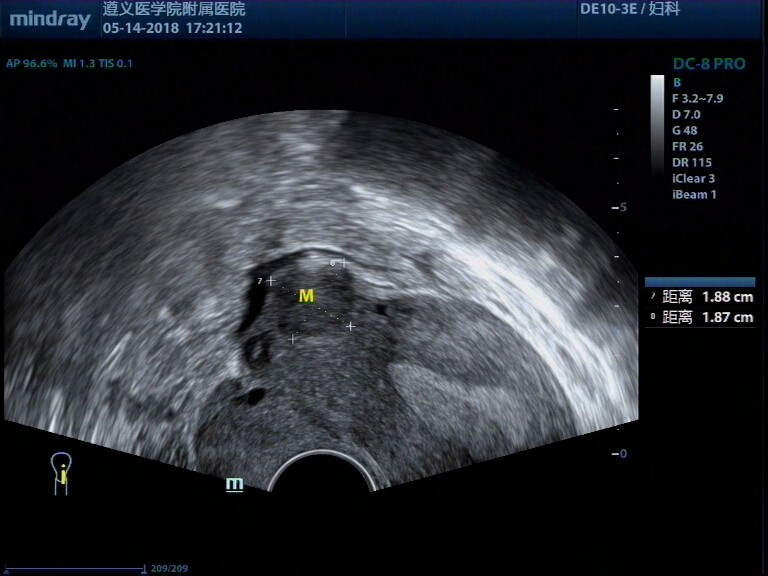

病例,31岁女性,纵膈子宫、畸胎瘤、子宫肌瘤

病例,31岁女性,纵膈子宫、畸胎瘤、子宫肌瘤。

病例来源遵义医学院附属医院